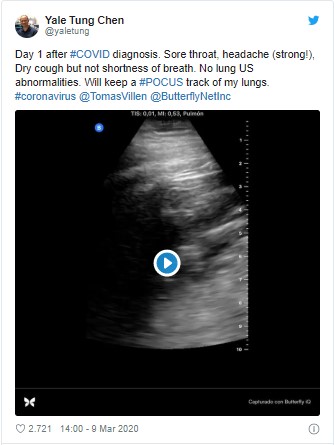

Madrid'de hastaları tedavi ederken koronavirüse yakalanan doktor, Kovid-19 hastası olmanın nasıl bir şey olduğu hakkında sosyal medyada ilk elden bilgi aktarıyor.

İspanya'da yaşayan 35 yaşındaki Doktor Yale Tung Chen, virüs ilerledikçe Twitter hesabında gelişmeleri paylaşıyor, semptomlardan bahsediyor ve hatta takipçileriyle akciğerlerinin ultrasonlarını paylaşıyor.

Dr. Chen daha sonra 9 Mart'ta semptomları hakkında günlük bilgiler paylaşmaya başladı.

İnternette oluşturduğu günlüğüne boğaz ağrısı, güçlü bir baş ağrısı ve kuru öksürüğü olduğunu fakat nefes darlığı çekmediğini söylediği bir tweet paylaşarak başladı.

Semptomlar hakkındaki bilgilerin yanı sıra Dr. Chen, akciğerlerinin ultrason videolarını paylaşarak virüsün nasıl ilerlediğine dair tıbbi analizini detaylandırdı.

İlk ultrason videosu şu an Twitter'da 140 binden fazla görüntülenmeye sahip ve 35 yaşındaki doktorun paylaşımlarına iyi dilek yorumları yağıyor.